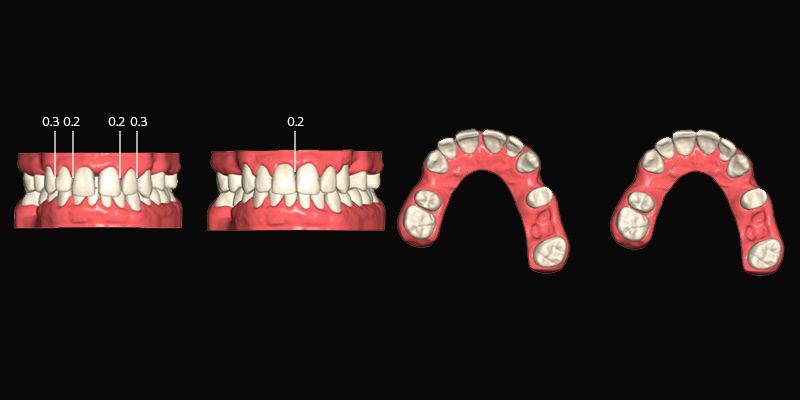

Los modelos digitales y registros de mordida se realizaron a partir de escaneados intraorales.

Se dieron las instrucciones para alinear y nivelar los seis dientes anteriores superiores, cerrando los espacios hacia mesial y mejorando la sobremordida con intrusión de los incisivos y especialmente del 23 que estaba más extruido.

El stripping en incisivos laterales superiores e incisivos inferiores no debía ser mayor a 0.3mm por lado.

El tratamiento se llevó a cabo en una primera fase de 12 alineadores Recode durante 4 meses.

Habiéndose conseguido los objetivos principales, persistió un ligero diastema entre 11 y 12 y fue necesario un ajuste del contacto 22-23 por lo que se decidió hacer un refinamiento de solo 4 alineadores Recode durante 30 días.